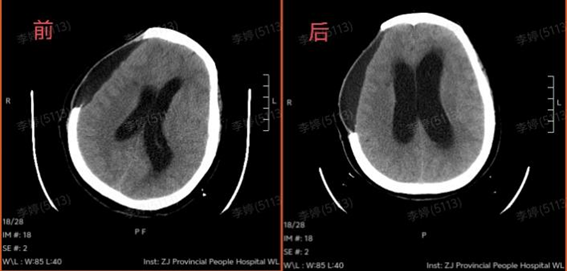

全家人也在积极配合。努力1个月后,王阿姨睁眼了,但眼神呆呆的,叫也没反应,手脚也不怎么动,好像整个人被“定”住了。头颅CT复查发现脑积水加重,脑脊液排不出,压住大脑,影响康复效果。